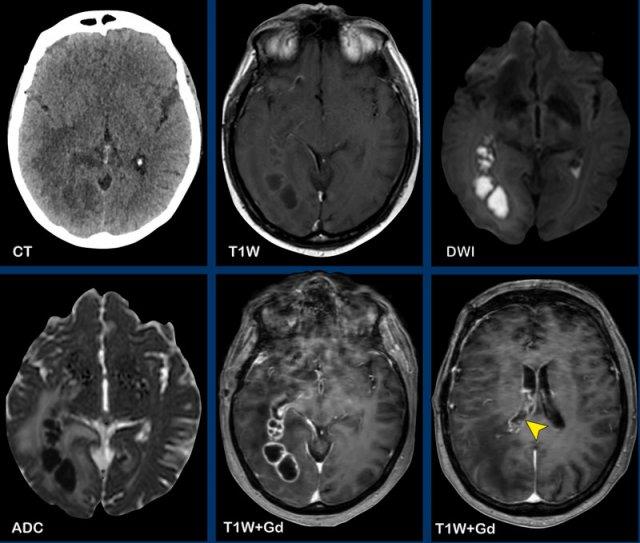

Các hình ảnh này của bệnh nhân có áp xe vùng đỉnh.

Hình ảnh

Áp xe biểu hiện hạn chế khuếch tán trung tâm với thành ngấm thuốc tương đối dày.

Đầu mũi tên màu vàng chỉ vào lớp ngấm thuốc mỏng của thành não thất.

Kết luận

Áp xe lan vào trong não thất, dẫn đến viêm não thất.

Các hình ảnh này của bệnh nhân nam 63 tuổi, có áp xe não nhỏ (mũi tên vàng) tại trung tâm bán bầu dục bên phải.

Lưu ý có sự xâm lấn não thất đáng kể.

Bên cạnh ngấm thuốc thành não thất, còn ghi nhận hạn chế khuếch tán trong áp xe và trong lòng não thất (đầu mũi tên).